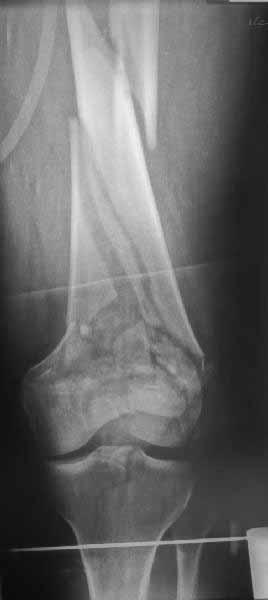

Ответ на эту часть Вашего поста – вложенный файл. Больная оперирована неделю назад по поводу открытого перелома дистального эпиметафиза бедренной кости. После операции она идёт в рентгенкабинет для выполнения послеоперационной контрольной рентгенографии, представленной на слайдах 10 и 11. Узнав, почему её фотографируют, просила передать Вам, Антон, привет.

наружный мыщелок не дорепонироавн - это приводит к вальгусной деформации оси коленного сустава, очень критично для последующей функции.

Рационально ориентироваться на качественный аспект - проблема или решается, или нет. Переломы типа 33C1 или C2 (то есть без фронтального раскалывания мыщелков, как на показанной Вами томограмме) при обычном качестве кости успешно можно фиксировать гвоздями с фронтальными винтами. Получается, их прочностных характеристик уже достаточно.

В приложении пример недавней операции, C3, открытая репозиция, фиксация мыщелков спицами и винтами, ретроградный синтез большеберцовым гвоздем 10,5 мм диаметром, винты 5 мм.